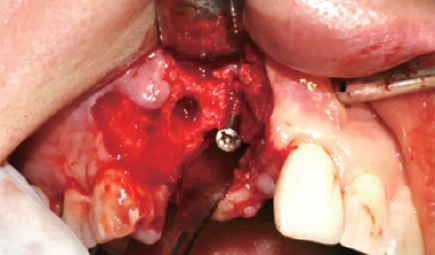

Case 1

수술 전

#45 Implant 식립

#47 Implant 식립

#45 & #46 부위 골 결손

#45 협측 골이식

Wifi-Mesh 준비 및 다듬기

#45 & #46 골 결손 부위에

Wifi-Mesh 위치시킴

#46 발치와 부위에 시행한

Open membrane technique